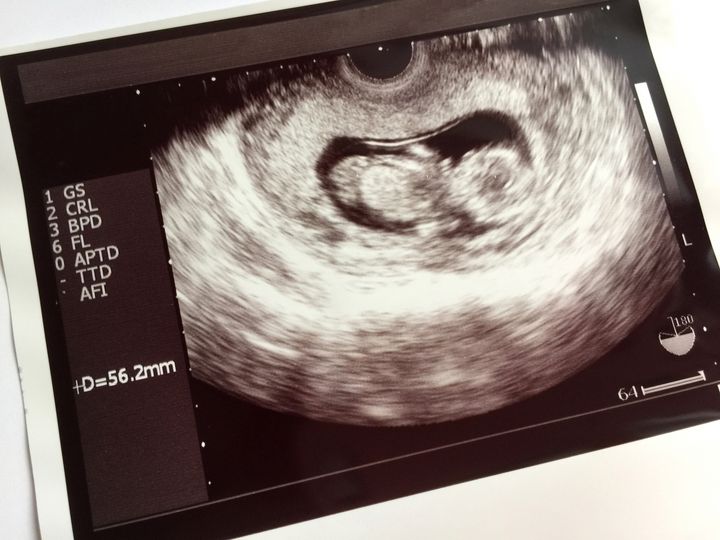

出典:photoAC(写真はイメージです)

妊娠中の検診で受け取るエコー写真。超音波検査によってお腹の中の胎児の様子を撮影した医療画像で、妊娠の経過を確認するために使用されます。

白黒の画面に映るぼんやりとした輪郭から、赤ちゃんの存在を実感できる機会。妊娠を望んでいた方からは、手のひらサイズの感熱紙に印刷されたその1枚は、家族にとってかけがえのない宝物となったという感想もよく聞かれます。